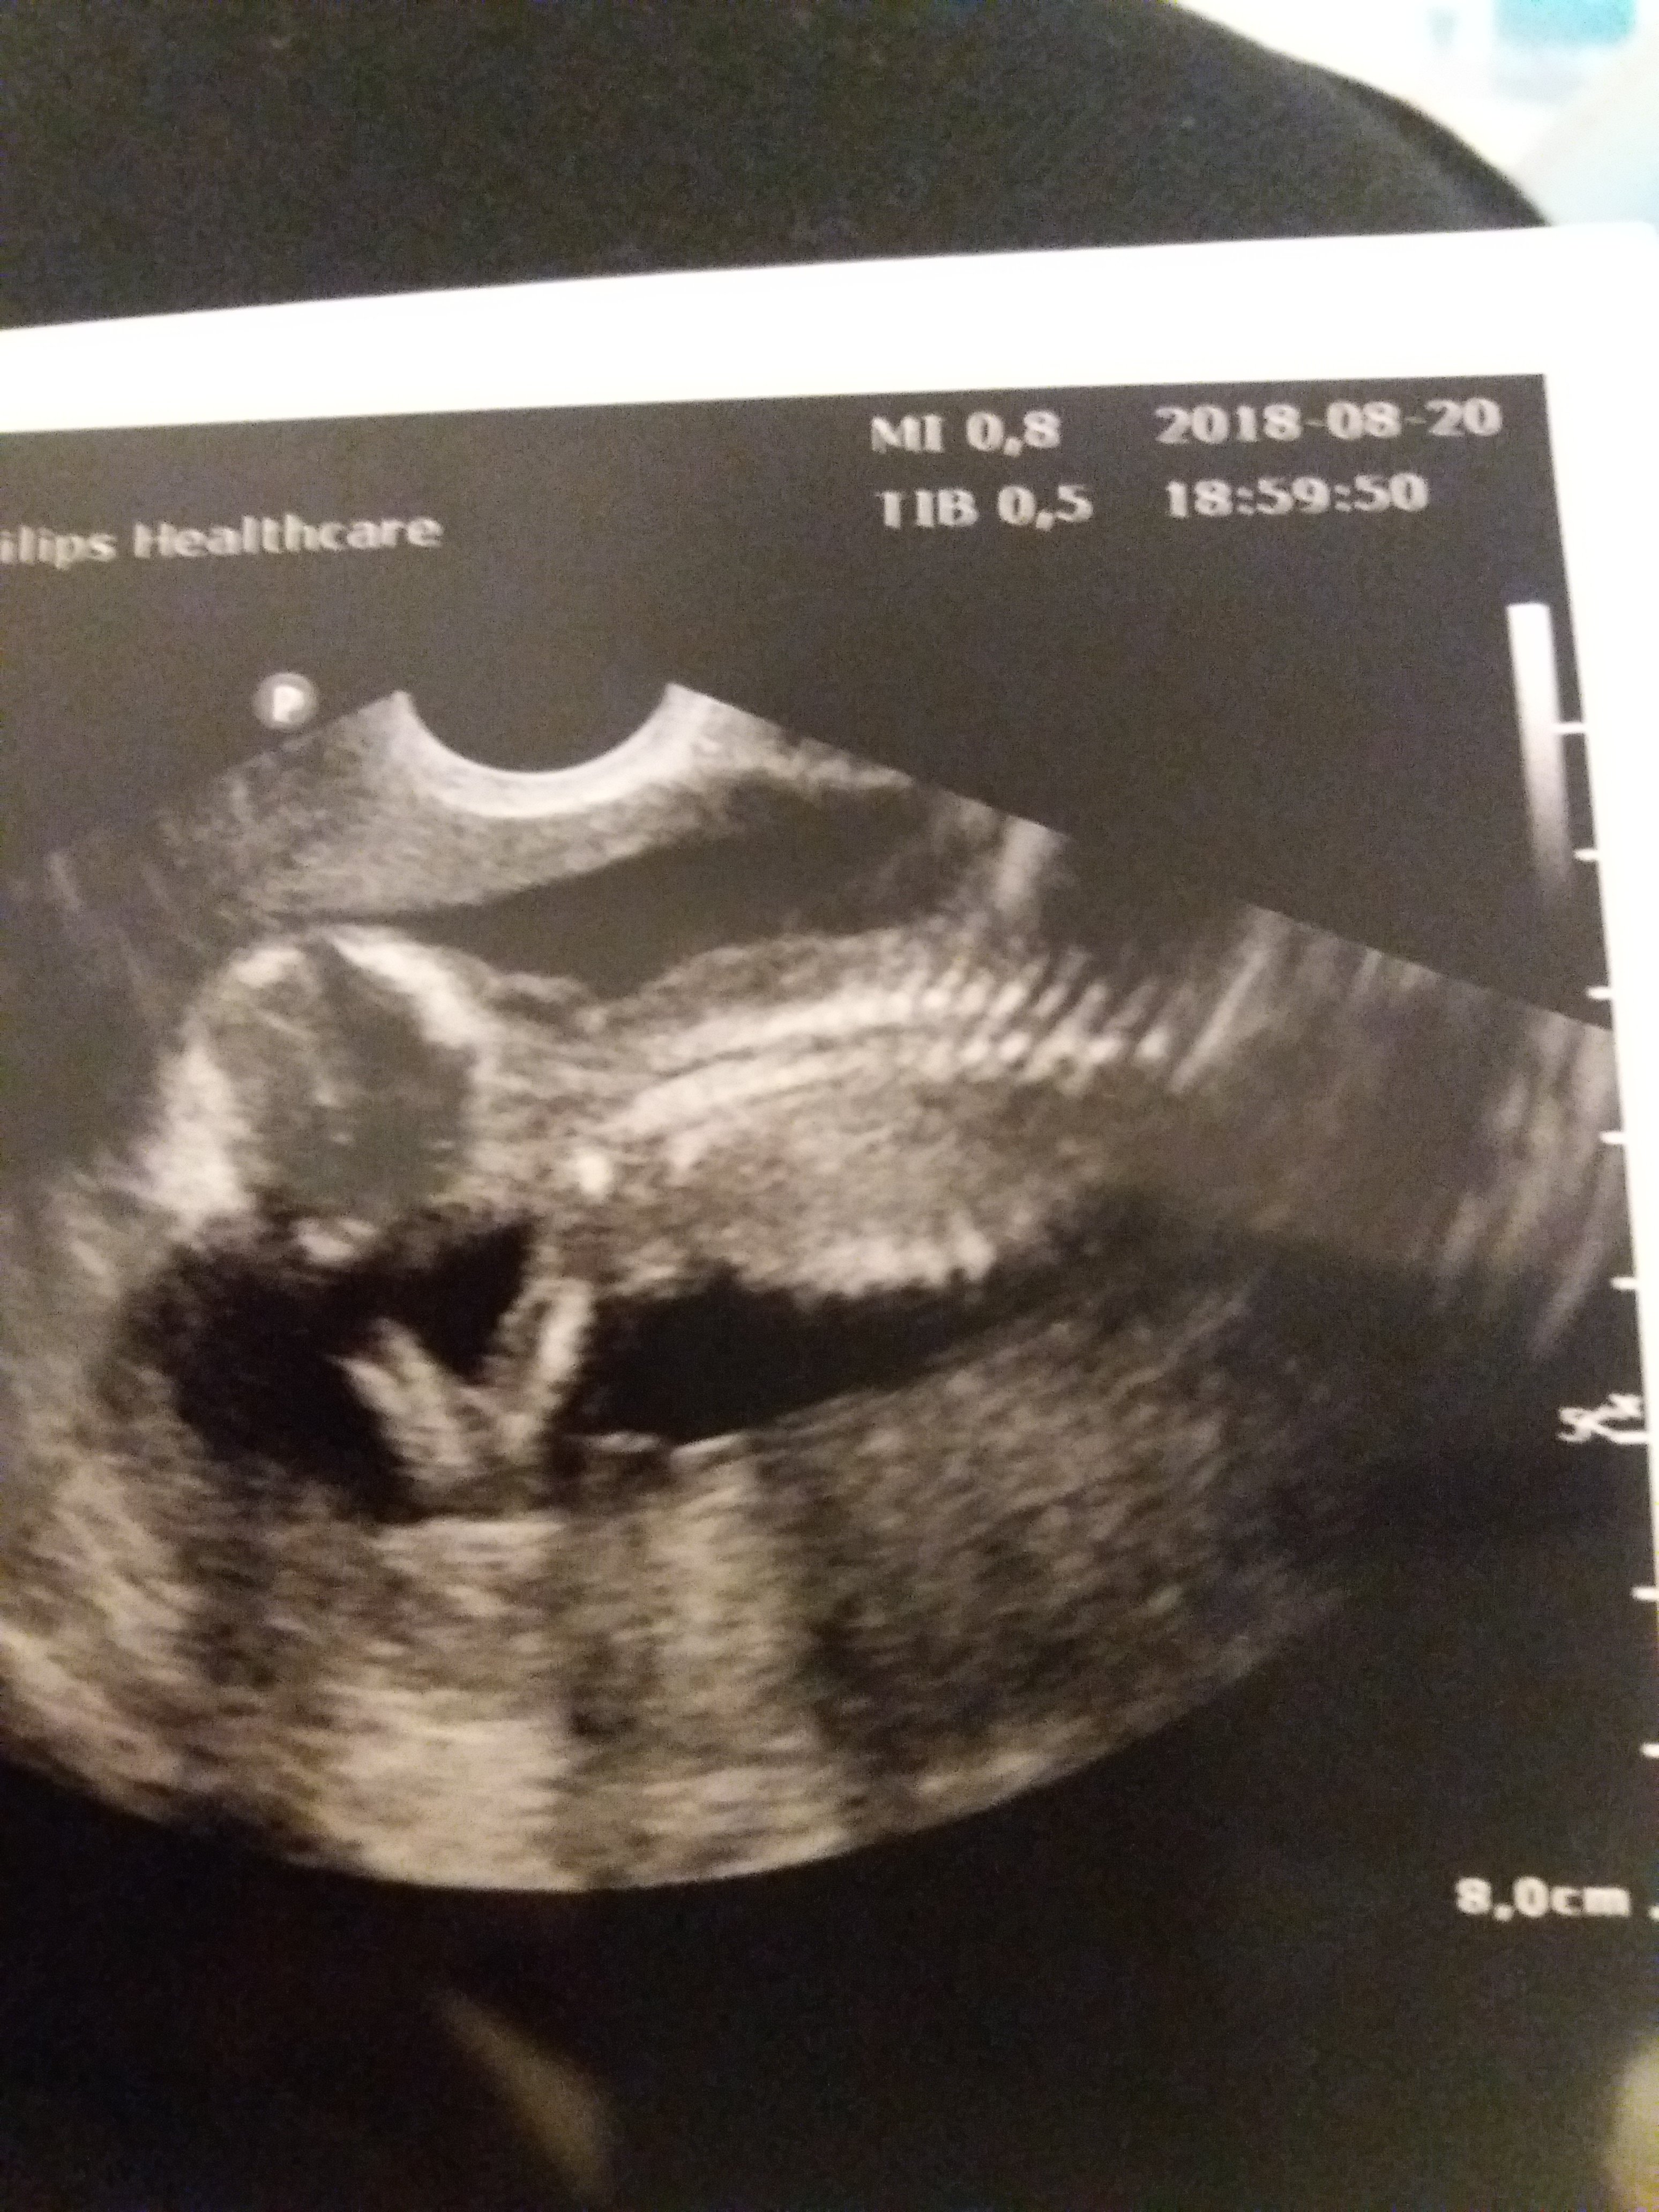

To u mnie dla odmiany wskazanie na chłopca, tak na 80 %. Parametry książkowe. Ale leniwy książę nie chciał się ujawnić, wolał relaks placami do nas.

Załączniki

• 20180820_202437.jpg

20180820_202437.jpg

1,8 MB · Wyświetleń: 117